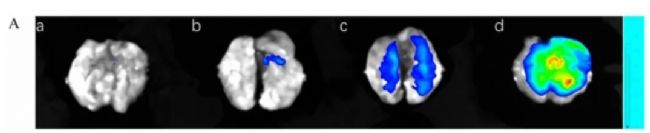

成像應(yīng)用:

利用Clinx勤翔 IVScope 8500小動(dòng)物活體成像系統(tǒng),對(duì)轉(zhuǎn)染熒光素酶的棕色脂肪細(xì)胞相關(guān)載體進(jìn)行活體成像,在C57BL/6J小鼠的肩胛間棕色脂肪組織(iBAT)中,評(píng)估Ucp1增強(qiáng)子(Ucp1-En4)對(duì)產(chǎn)熱功能的影響。

成像結(jié)果:

冷適應(yīng)條件下,靶向抑制Ucp1-En4的小鼠iBAT區(qū)域熒光信號(hào)強(qiáng)度降低,伴隨直腸溫度和背部皮膚溫度顯著下降,證實(shí)Ucp1-En4通過調(diào)控Ucp1表達(dá)影響棕色脂肪產(chǎn)熱。透射電鏡與生化分析顯示,Ucp1-En4抑制導(dǎo)致iBAT線粒體結(jié)構(gòu)異常、mtDNA含量減少,表明該增強(qiáng)子是維持線粒體功能和產(chǎn)熱的關(guān)鍵調(diào)控元件。